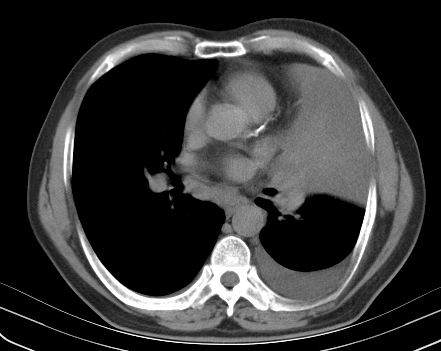

以下是引用老爱克斯新网客在2008-7-31 6:30:00的发言:[br]左肺上叶大片状病灶,左肺上叶支气管狭窄呈鼠尾状,左肺门增大,纵隔内见肿大淋巴结,左侧胸腔积液,余肺清晰。左肺中心型肺癌淋巴结转移,

以下是引用zjzjr在2008-7-31 8:45:00的发言:[br]考虑左侧中心性肺癌伴阻塞性肺炎,左肺上叶肺不张,纵隔淋巴结转移;左侧胸腔积液。建议行纤支镜检查。

以下是引用zjb在2008-7-31 6:32:00的发言:[br]左侧中心性肺癌 阻塞性肺炎 肺不张 胸腔积液 建议气管镜

以下是引用sdzyy在2008-7-31 8:47:00的发言:[br]病灶较治疗前有所进展,胸水增多, 左侧中心性肺癌 并 阻塞性肺炎 肺不张 胸腔积液 可能性大; 建议气管镜检查。 [br] [br]